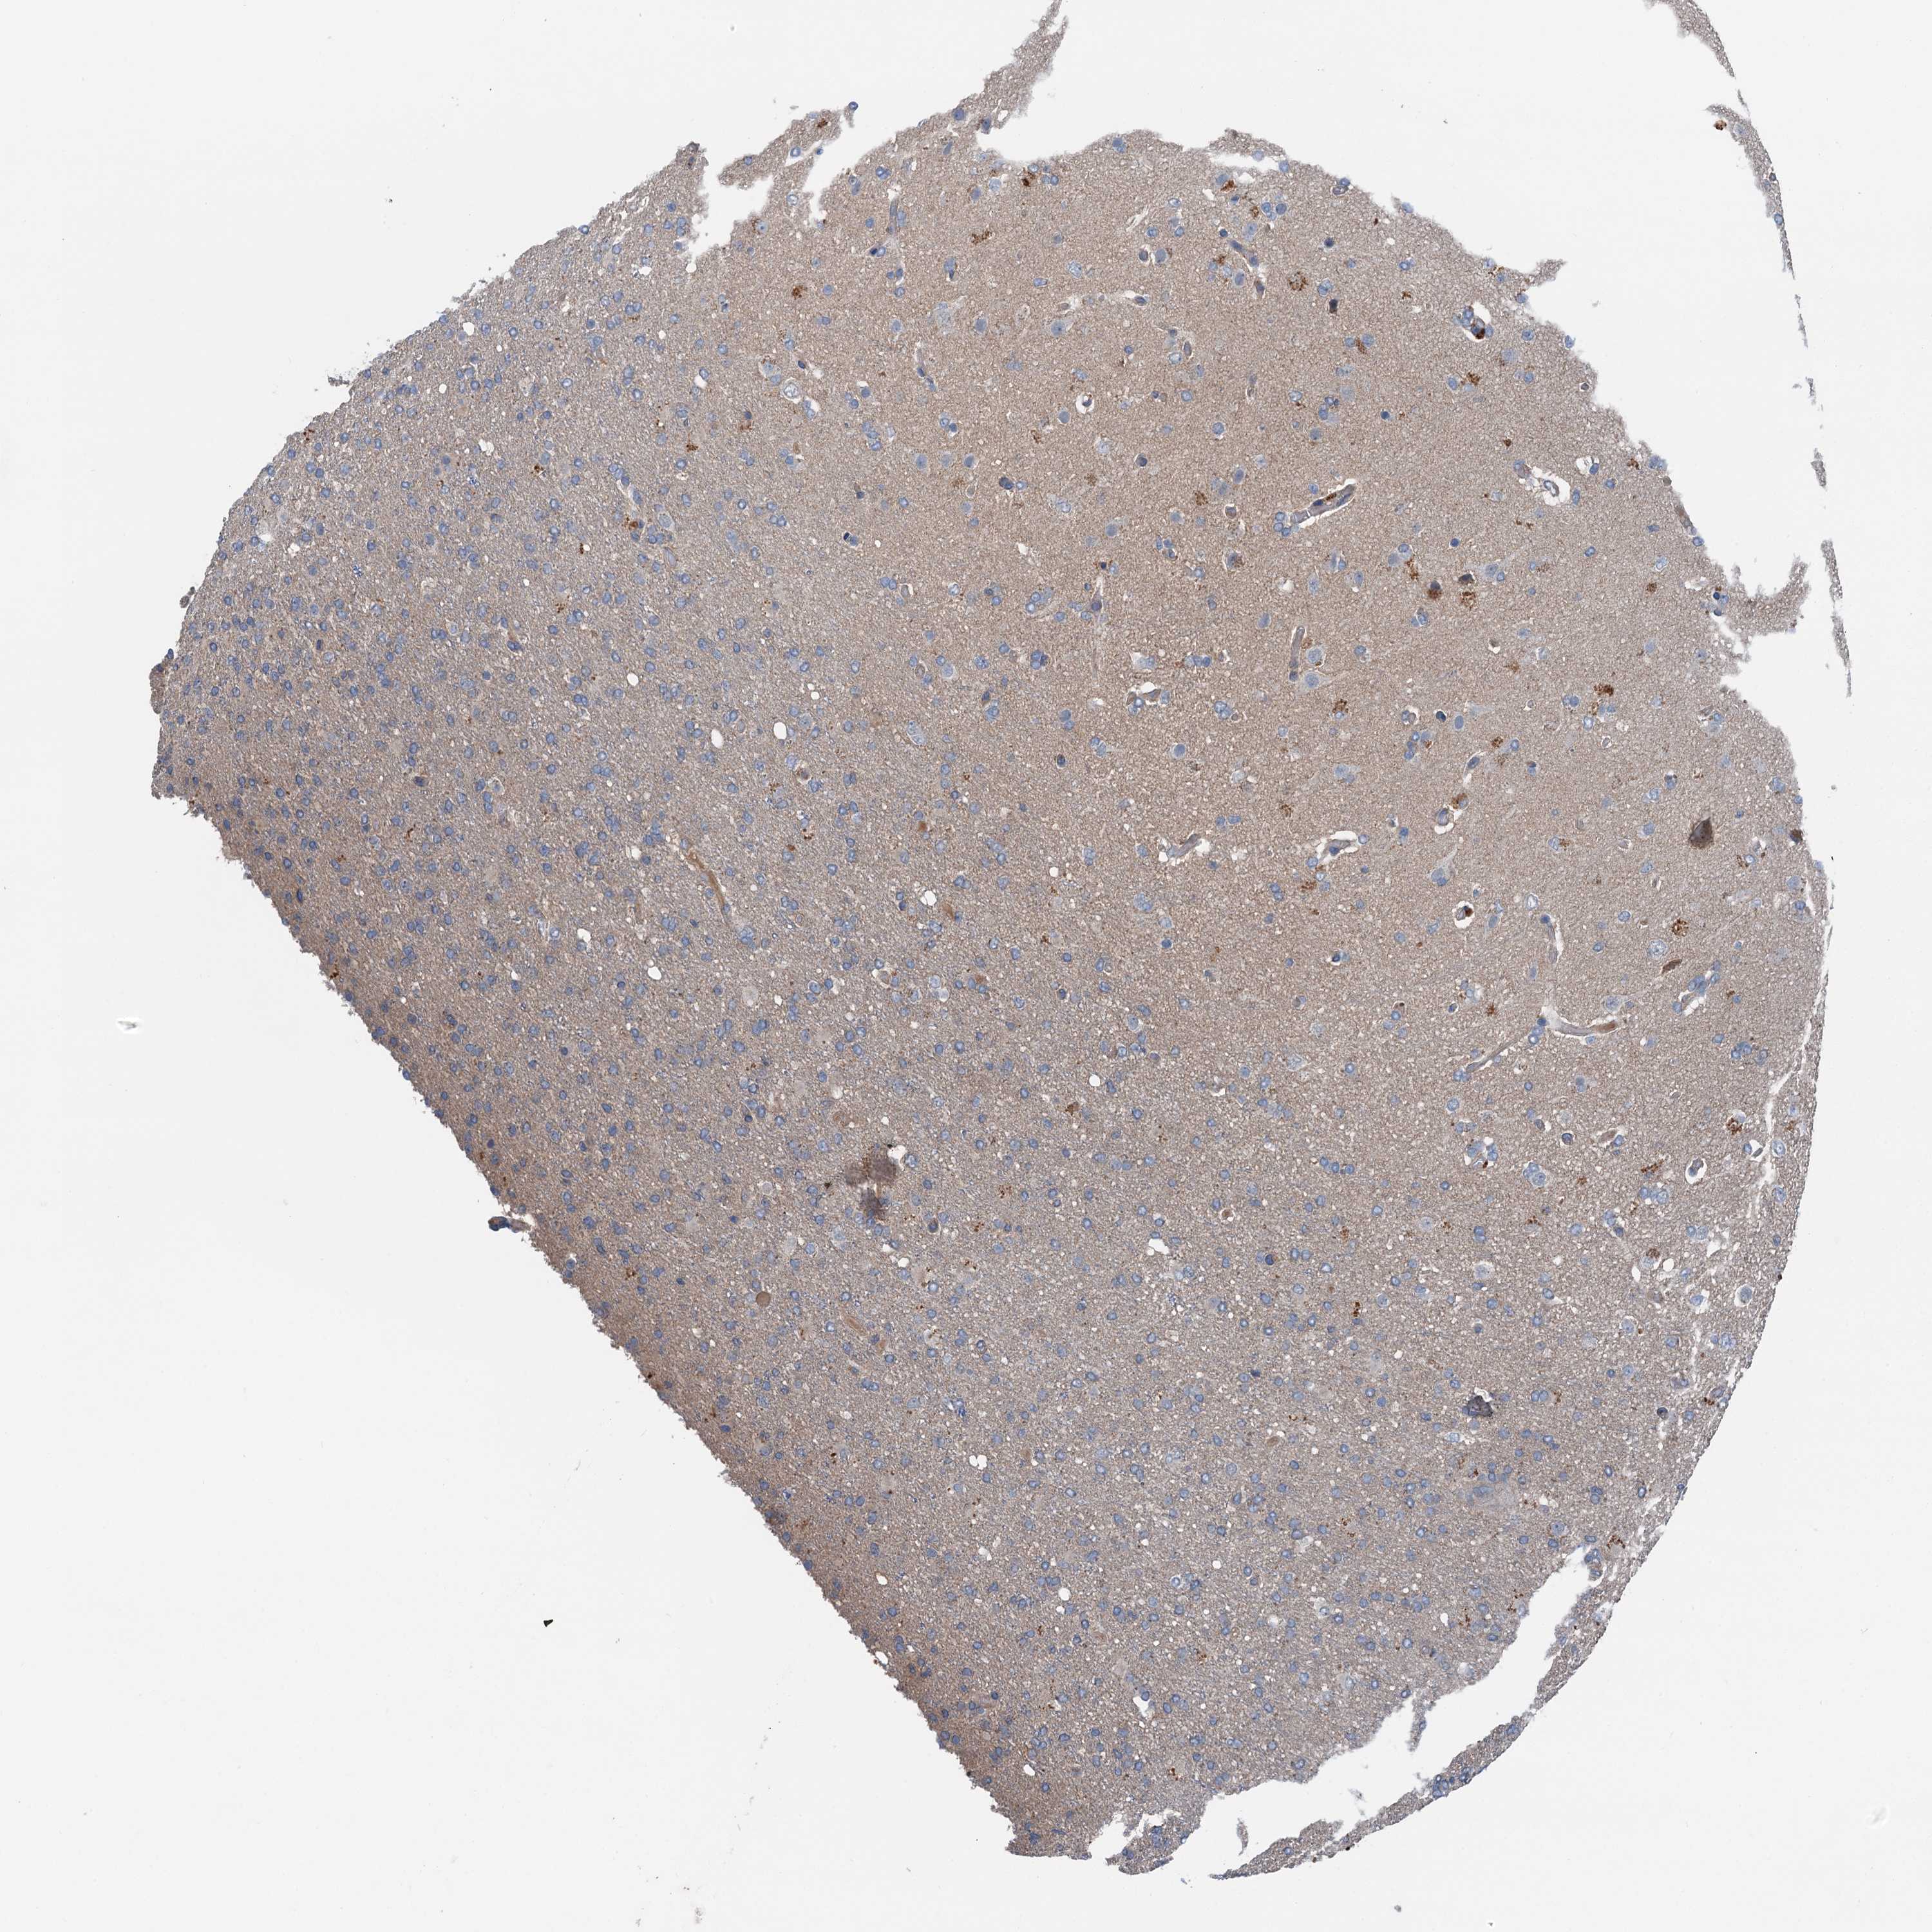

GLIOMA - Protein expressioni

A mouse-over function shows sample information and annotation data. Click on an image to view it in a full screen mode. Samples can be filtered based on level of antibody staining by selecting one or several of the following categories: high, medium, low and not detected. The assay and annotation is described here.

Note that samples used for immunohistochemistry by the Human Protein Atlas do not correspond to samples in the TCGA dataset.

Antibody stainingi

Antibody staining in the annotated cell types in the current human tissue is reported as not detected, low, medium, or high, based on conventional immunohistochemistry profiling in selected tissues. This score is based on the combination of the staining intensity and fraction of stained cells.

Each image is clickable and will lead to virtual microscopy that enables deeper exploration of all samples and also displays staining intensity scores, fraction scores and subcellular localization as well as patient and tissue information for each sample.

Antibody HPA041015

Staining

High

Medium

Low

Not detected

Intensity

Strong

Moderate

Weak

Negative

Quantity

>75%

75%-25%

<25%

None

Location

Nuclear

Cytoplasmic/membranous

Cytoplasmic/membranous,nuclear

Glioma, malignant, High grade

Glioma, malignant, Low grade